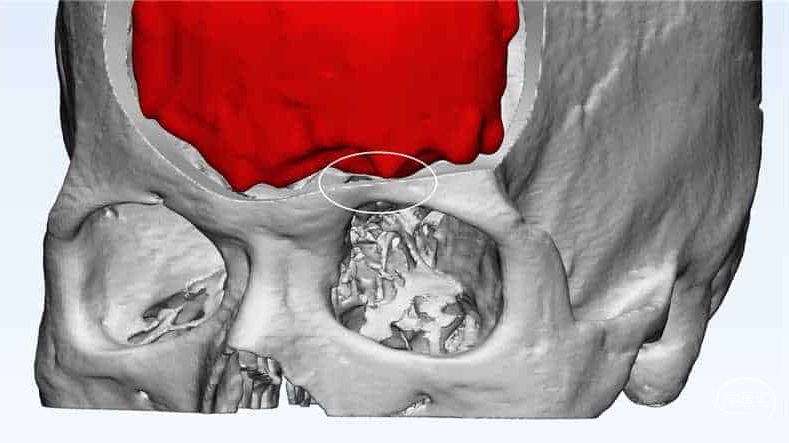

影像重建

肿瘤与静脉、矢状窦的关系

静脉影像重建

CT重建

左额内外板可见骨质增生